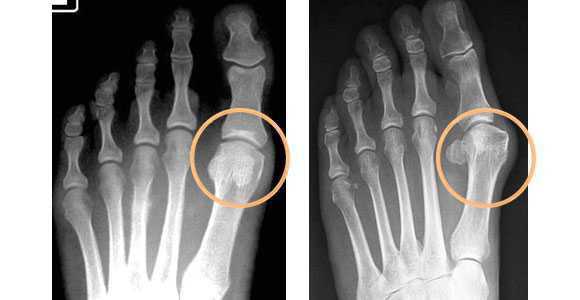

- Поперечное. Диагностируется в 55-80% случаев. Обычно развивается у людей среднего возраста (35-50 лет). Женщины страдают в 20 раз чаще мужчин. Этот вид плоскостопия характеризуется уменьшением длины стопы, веерообразным расхождением костей плюсны, деформацией I пальца (Hallux valgus), которую в быту обычно называют «косточкой», и молоткообразными пальцами стопы.

Опора перераспределяется на головки всех плюсневых костей, при этом нагрузка на головку I плюсневой кости уменьшается, а нагрузка на головки II-IV плюсневых костей резко увеличивается. I палец отклоняется кнаружи, головка I плюсневой кости и I палец образуют угол. В I плюснефаланговом суставе возникает остеоартроз. Появляются боли, уменьшается объем движений в суставе.

При уплощении поперечного свода распластывание характеризуется расхождением пальцев и увеличением ширины стопы. [13] Поэтому определение степени тяжести плоскостопия происходит путем измерения угла между 1 и 2 плюсневыми костями:

Поперечный свод стопы — это арка, которая состоит из 5 плюсневых костей. Вершиной этой арки является 2-я плюсневая кость. В норме стоя мы опираемся на три точки — пятку и головки 1-й и 5-й плюсневых костей. При плоскостопии головки 2-й и 4-й пальцев опускаются и становятся в один ряд с 1-й и 5-й костями.

Снимки в двух проекция выполняются поочерёдно для обоих ног. Степень поперечного плоскостопия определяют по углу отклонения 1-й плюсневой кости и большого пальца. На рентгенограммах проводят три прямые линии, соответствующие продольным осям 1-й и 2-й плюсневой кости и основной фаланге большого пальца [2] .